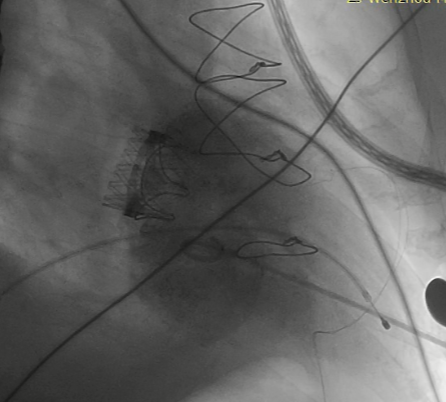

猪尾导管过瓣环平面进左心房

交换加硬导丝

扩张鞘预扩心尖穿刺点

输送器进入左室至生物瓣下方

左房内未见对比剂显影